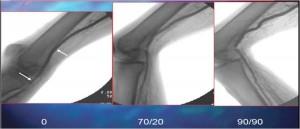

Popliteal kinking er teoretisert som en av årsakene til stentfeil i poplitealområdet. I en interessant studie av 68 pasienter som ble angiografert av poplitealarterien, ble det identifisert et hengselpunkt hos 98,6% av pasientene (Diaz et al. (1), se figur 1).

Bilde brukt med tillatelse fra Dr. Chris Metzger, direktør for hjerte- og perifere laboratorier ved Holston Valley, Kingsport Tennessee. På grunn av den indre bevegelsen av kneleddet og dannelsen av et hengselpunkt, er bruk av PTA alene, selvutvidende stenter med knusresistente egenskaper og endovaskulære stenttransplantater, blitt studert mye. Den gjennomsnittlige patency-graden av poplitealarterien etter PTA alene er ca. 47% etter 2 år. Jo lengre lesjonens lengde, desto høyere er restenosene. (referanse 1, referanse 2, referanse 3).